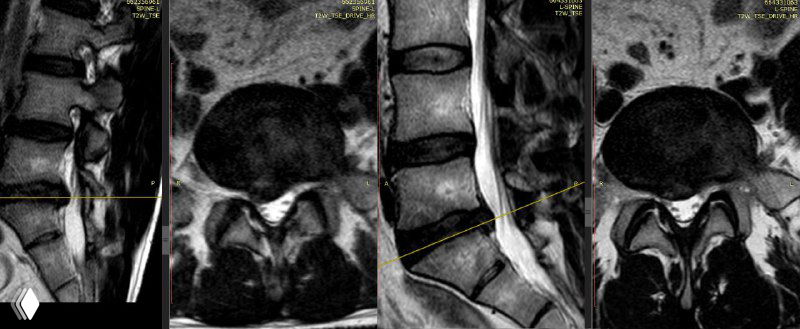

Пожилой пациент с рецидивом поясничной грыжи (парамедианно‑фораминальное с экстрафораминальным компонентом). МРТ показала крупный рецидив; после третьей операции боль ушла.